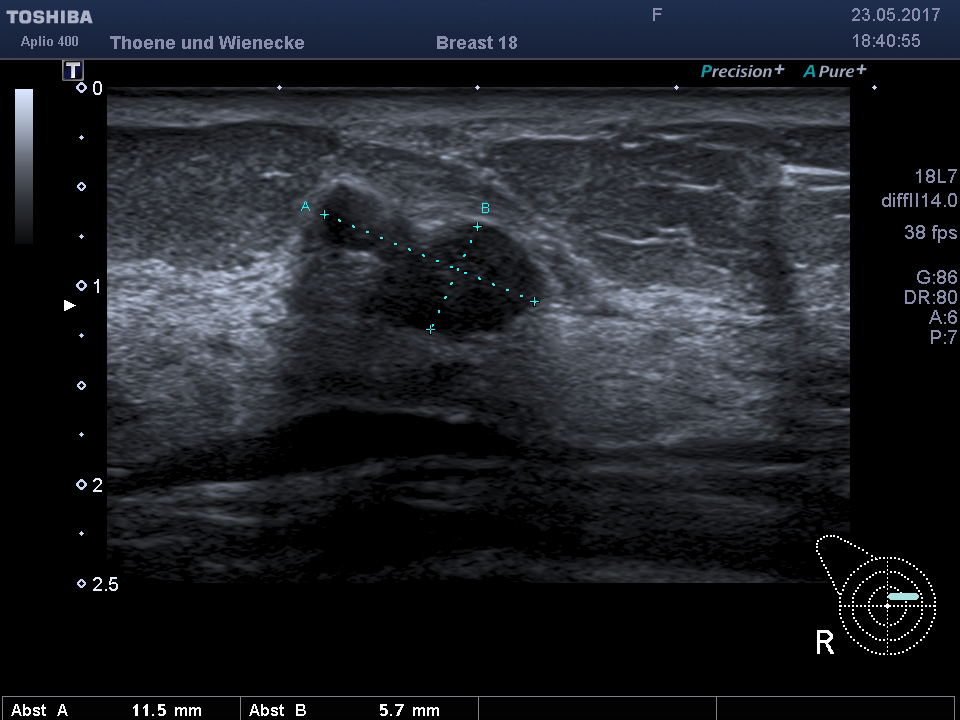

Der Ultraschall ist eine Untersuchung ohne Strahlenbelastung. In unsrer Praxis werden hochauflösende Ultraschallköpfe verwendet, die eine hohe Genauigkeit und sehr gute Auflösung ermöglichen. D.h. auch kleinste Veranderungen können schon gesehen werden. Mit der 3 D Sonographie können Veränderungen des Gewebes in ihrer Abgrenzung zum normalen umgebenden Gewebe besser beurteilt werden als nur mit der 2 D Methode. Bösartige Knoten bilden Ausläufer in das umgebende Gewebe, die wie kleine Strahlen einwachsen. Diese Phämomene können mit der 3 D Sonographie beurteilt werden, die Unterscheidung zwischen gutartigen und bösartigen Veränderungen wird genauer und die Rate an unnötigen Biopsien kann vermindert werden.